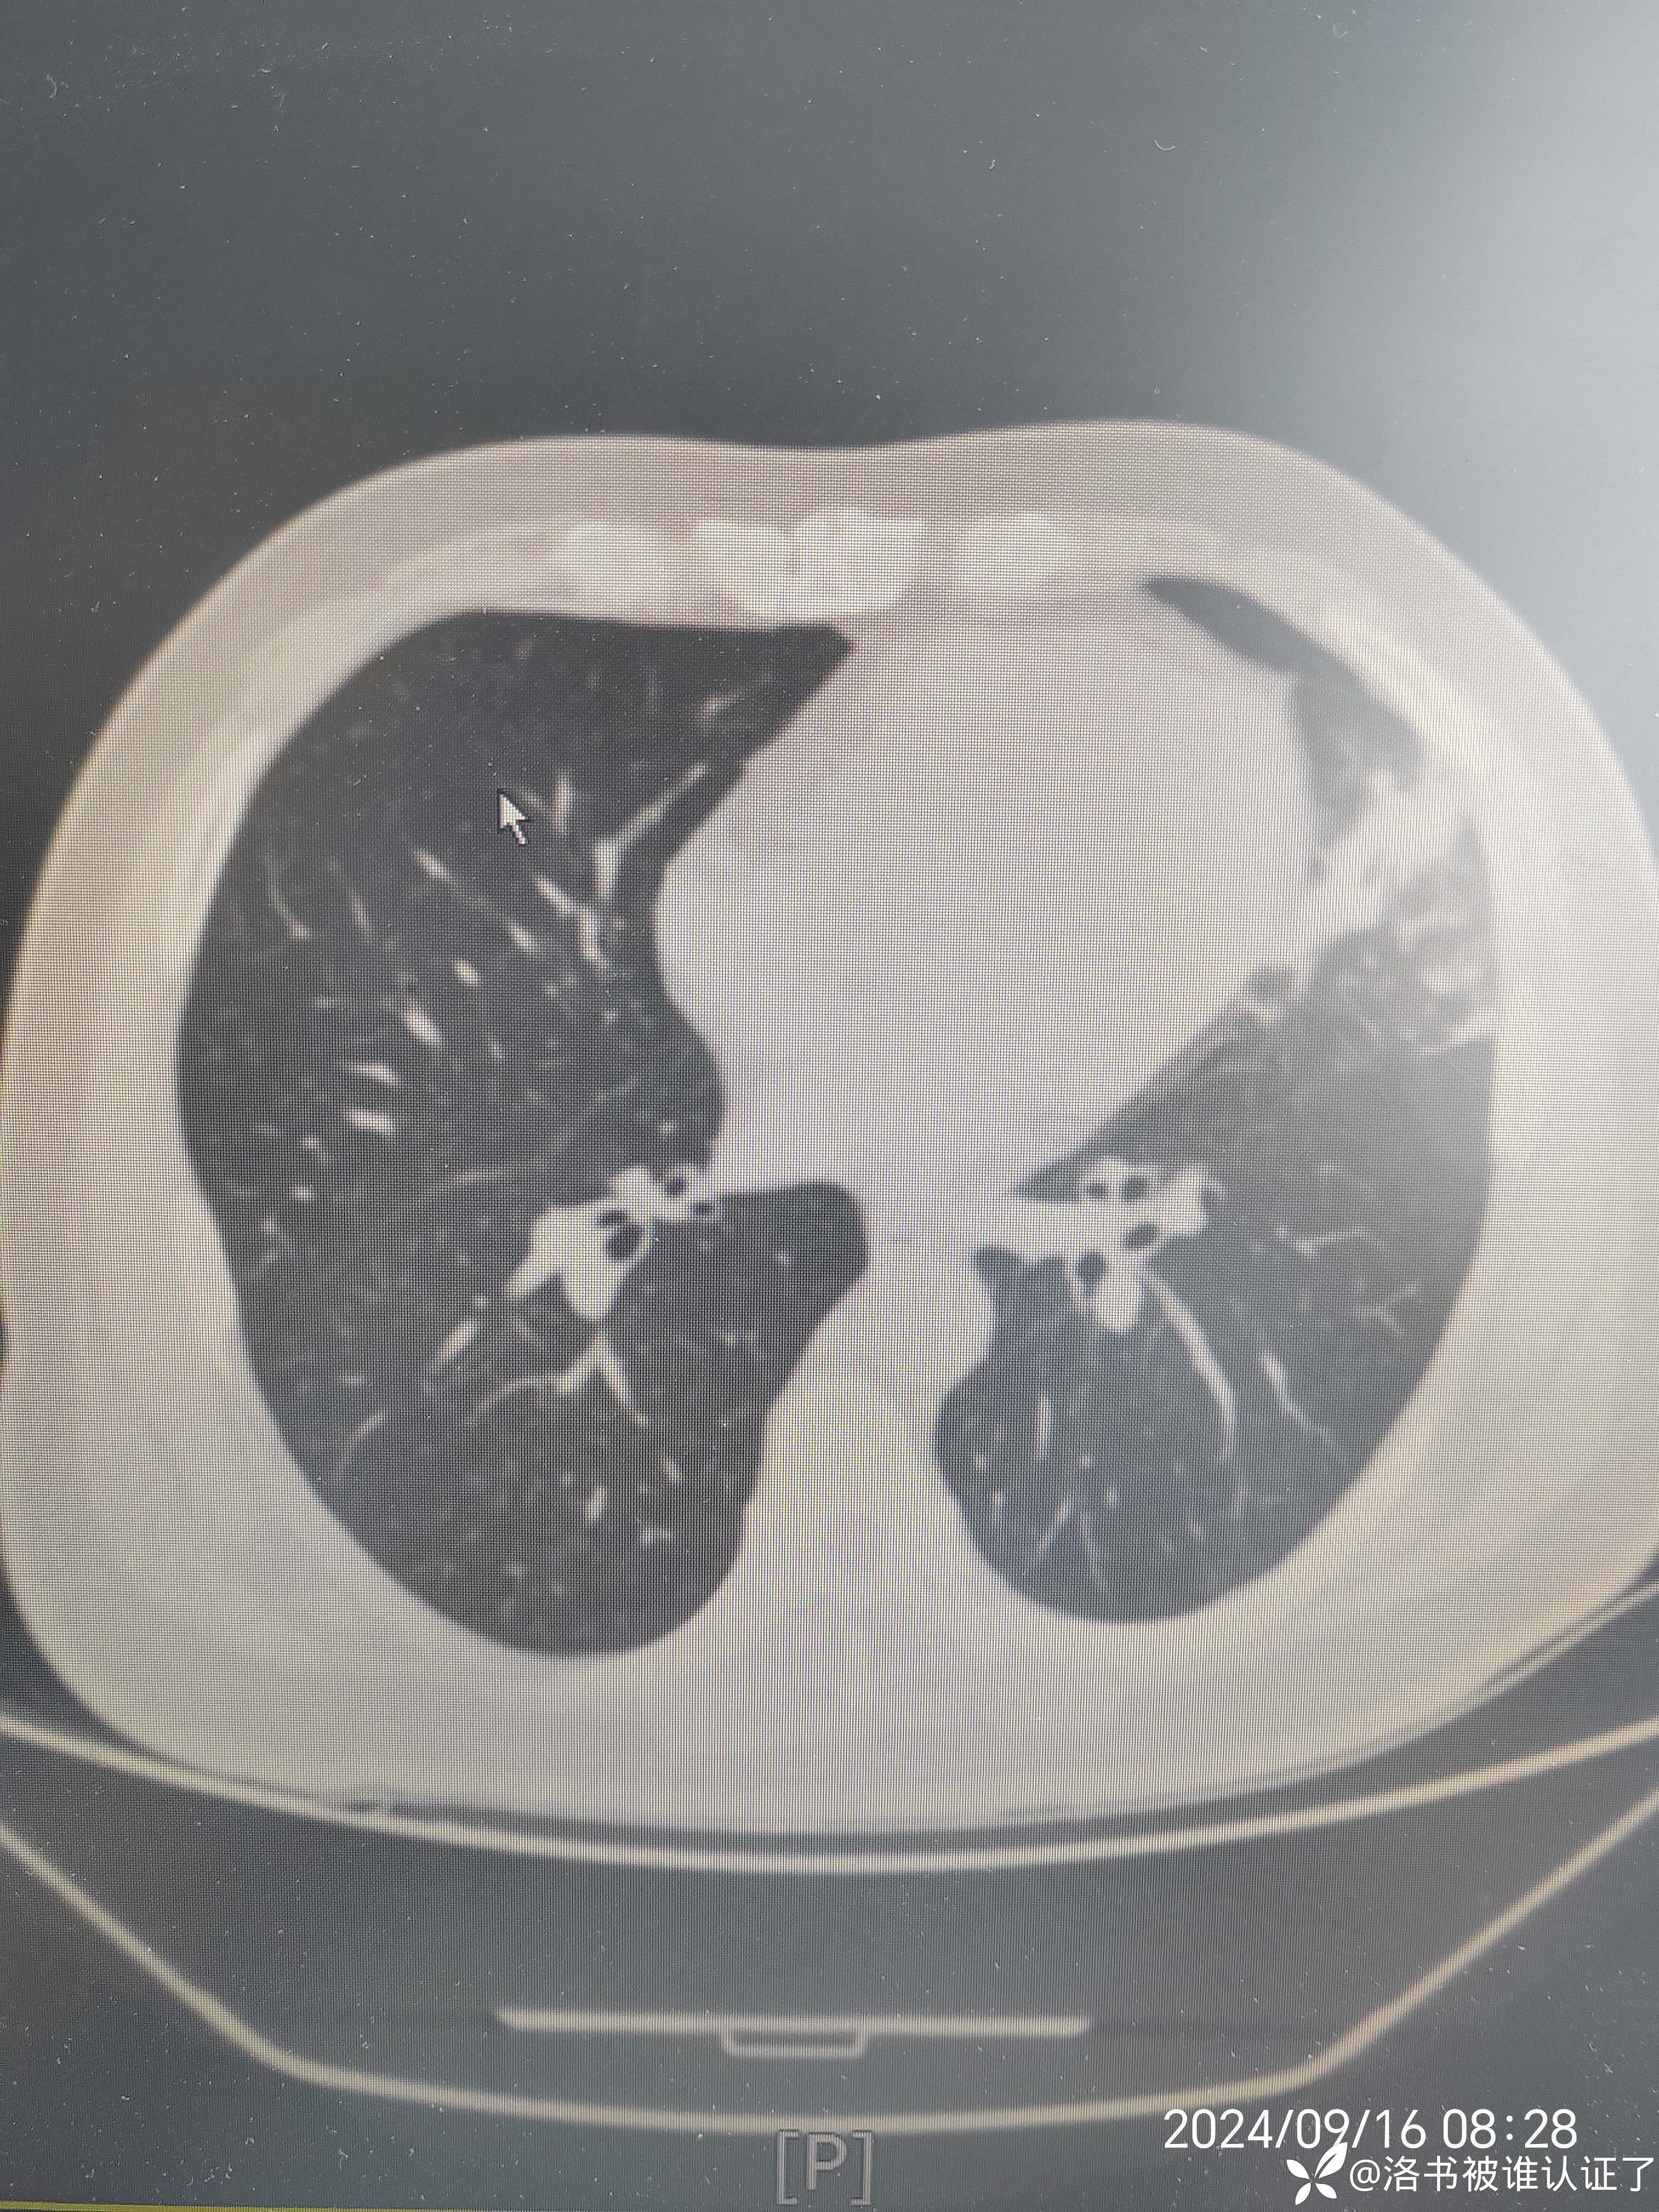

【检查】胸部CT示肺炎。

【临床诊断】:肺炎